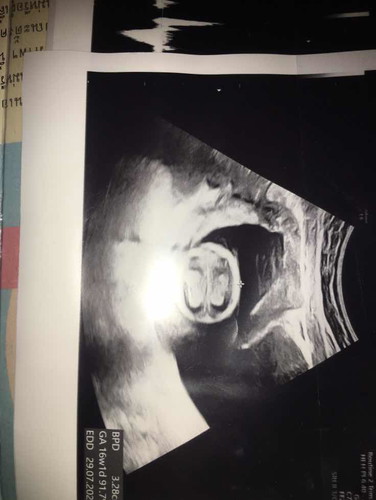

ส่วนหัวค่ะ ประมาณ 4 เดือน คุณหมอจะวัดกะโหลกเพื่อดูอายุค่ะ

ส่วนหัวน้องค่ะแม่ ข้างในคือโพรงสมองของน้องค่ะ

คุณหมอกำลังวัดขนาดศีรษะลูกค่ะ

หัวค่ะข้างในเป็นสมองค่ะ